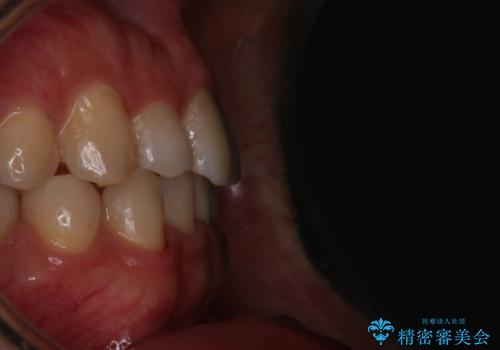

- 前歯のがたつきを主訴に来院されました。初診時、右上2番の口蓋側転位と右下7番の舌側傾斜が認められました。

インビザラインにてIPRと歯列弓拡大を行い、ゴム掛けで噛み合わせを改善する治療計画を立てました。

マウスピースの使用時間が短いため、シュミレーション通り進むか不安でしたが

治療期間1年で、主訴である前歯のがたつきを改善出来、

奥歯の噛み合わせも良くなりました。